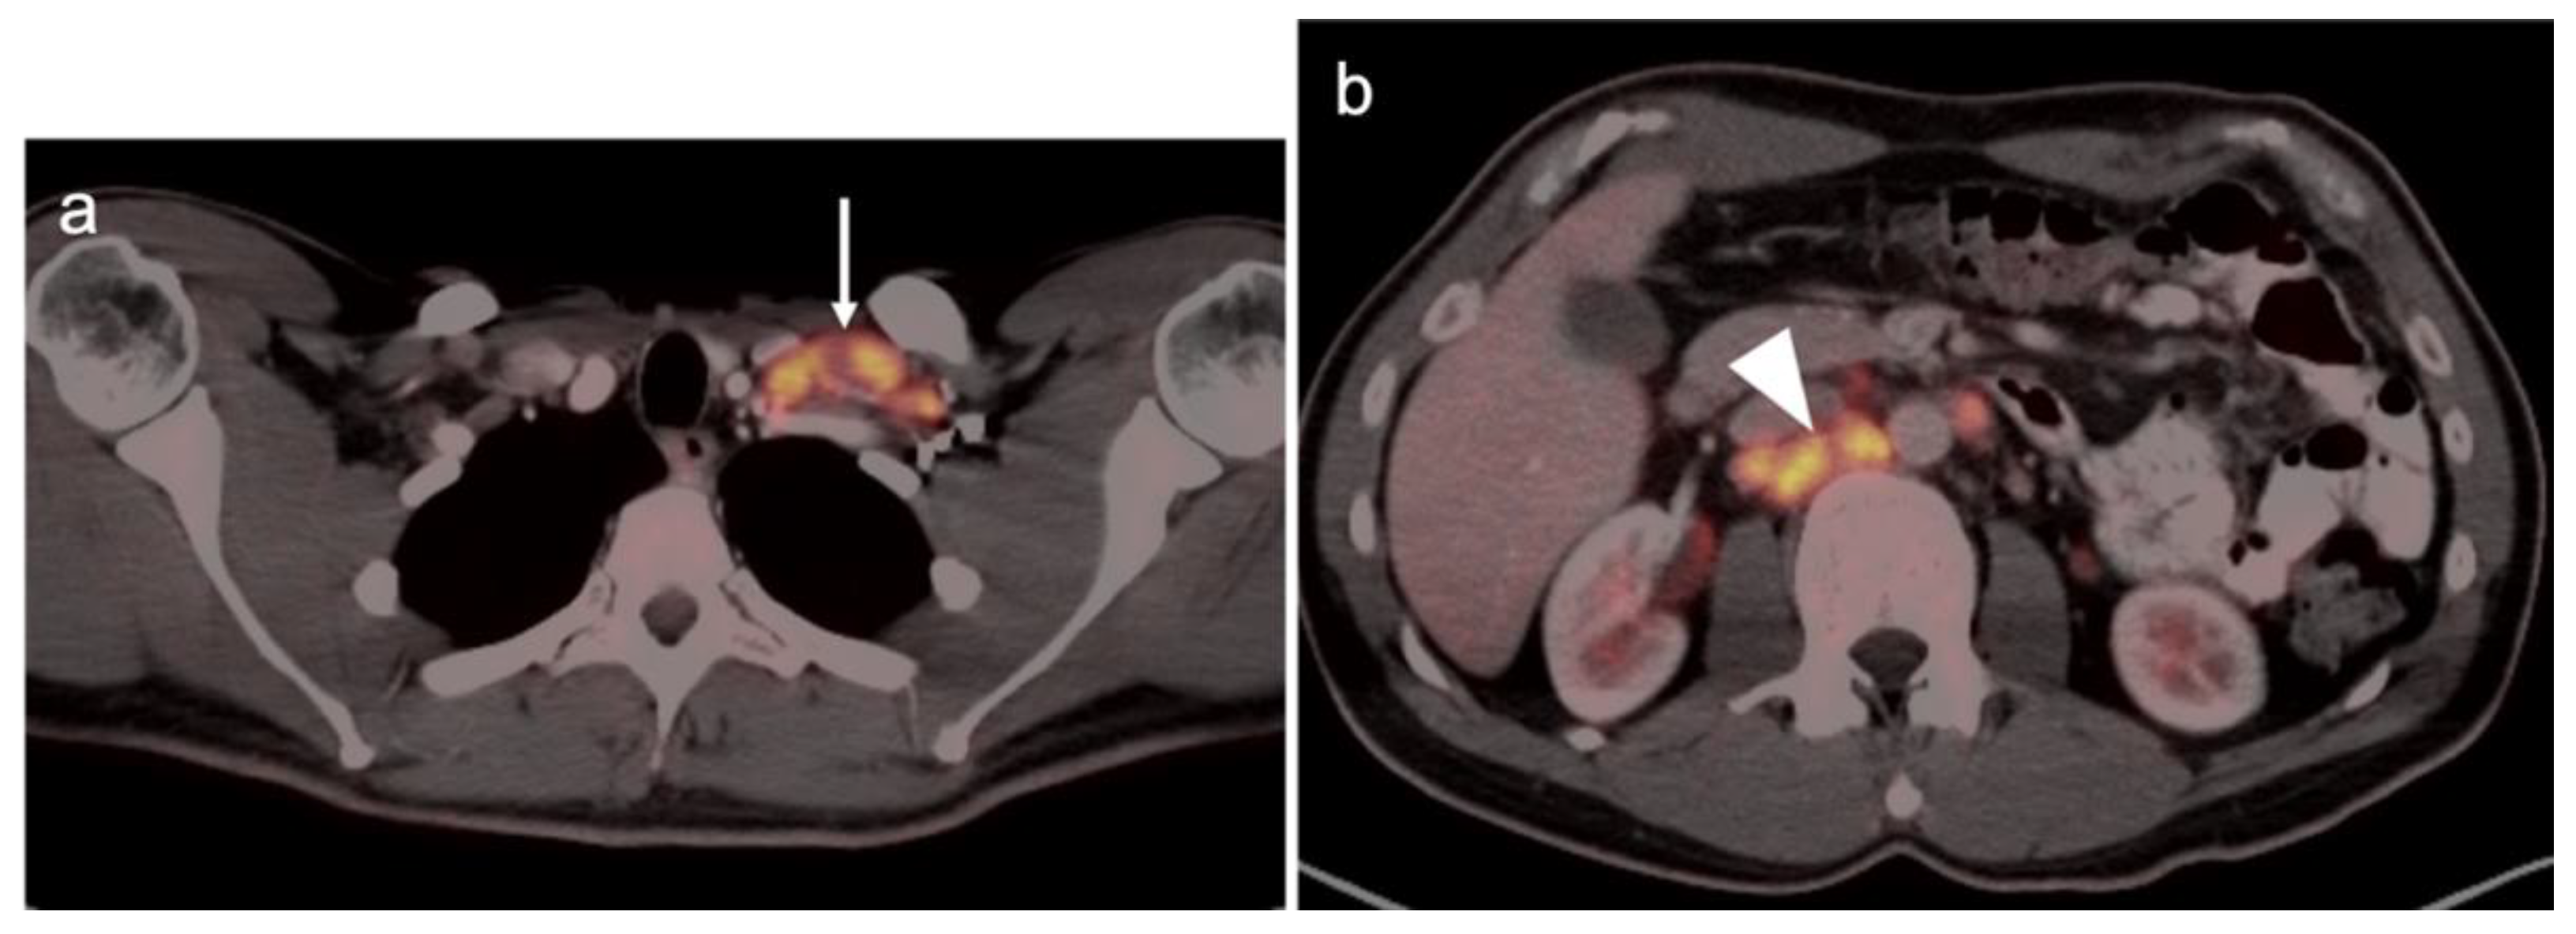

Abstract

3. Urological Malignancies

3.1. Prostate Cancer

3.2. Urothelial Carcinoma